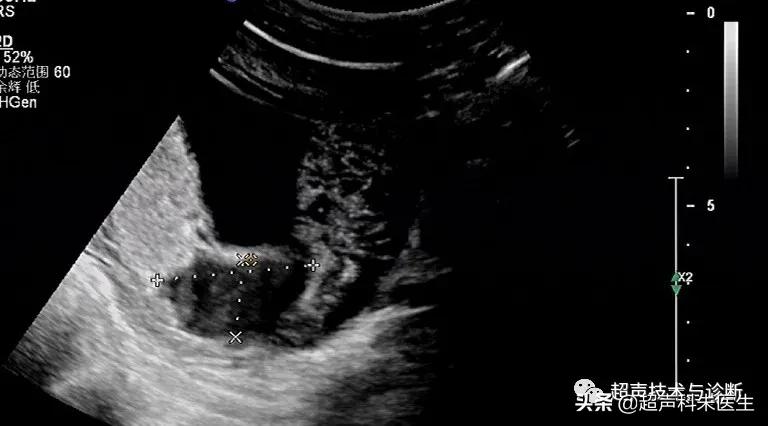

出现绒毛膜下血肿的孕妇,仅有20%会出现阴道不规则流血或下腹部疼痛的症状,而其余大多数绒毛膜下血肿是在超声检查中发现的,其超声表现为:子宫壁和胎膜(或孕囊)之间的无回声区,多位于胎盘下缘至宫颈内口间,以弧形或新月形多见,若血肿较多或血肿形成时间较长时,内可见点、絮状弱回声及条带状强回声,彩色多普勒超声检查:血肿内无血流信号。

接下来我们来看看具体病例: